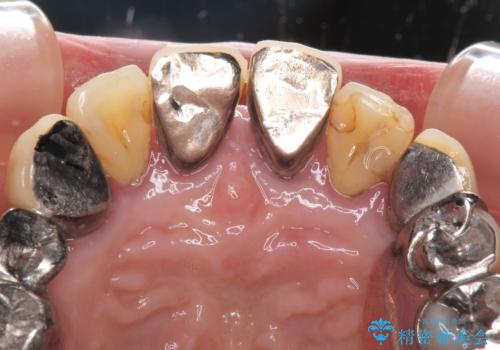

- 歯茎からの出血、入れ歯、歯の欠損、デコボコの前歯などを気にして来院された患者様です。

まずは抜歯が必要な歯を抜歯した上で仮歯に置き換え、インプラント埋入や歯周外科処置、根管治療を行うこととしました。

インプラントに対する恐怖心が強く、欠損補綴は極力ブリッジを採用し、インプラントの数は必要最小限としました。